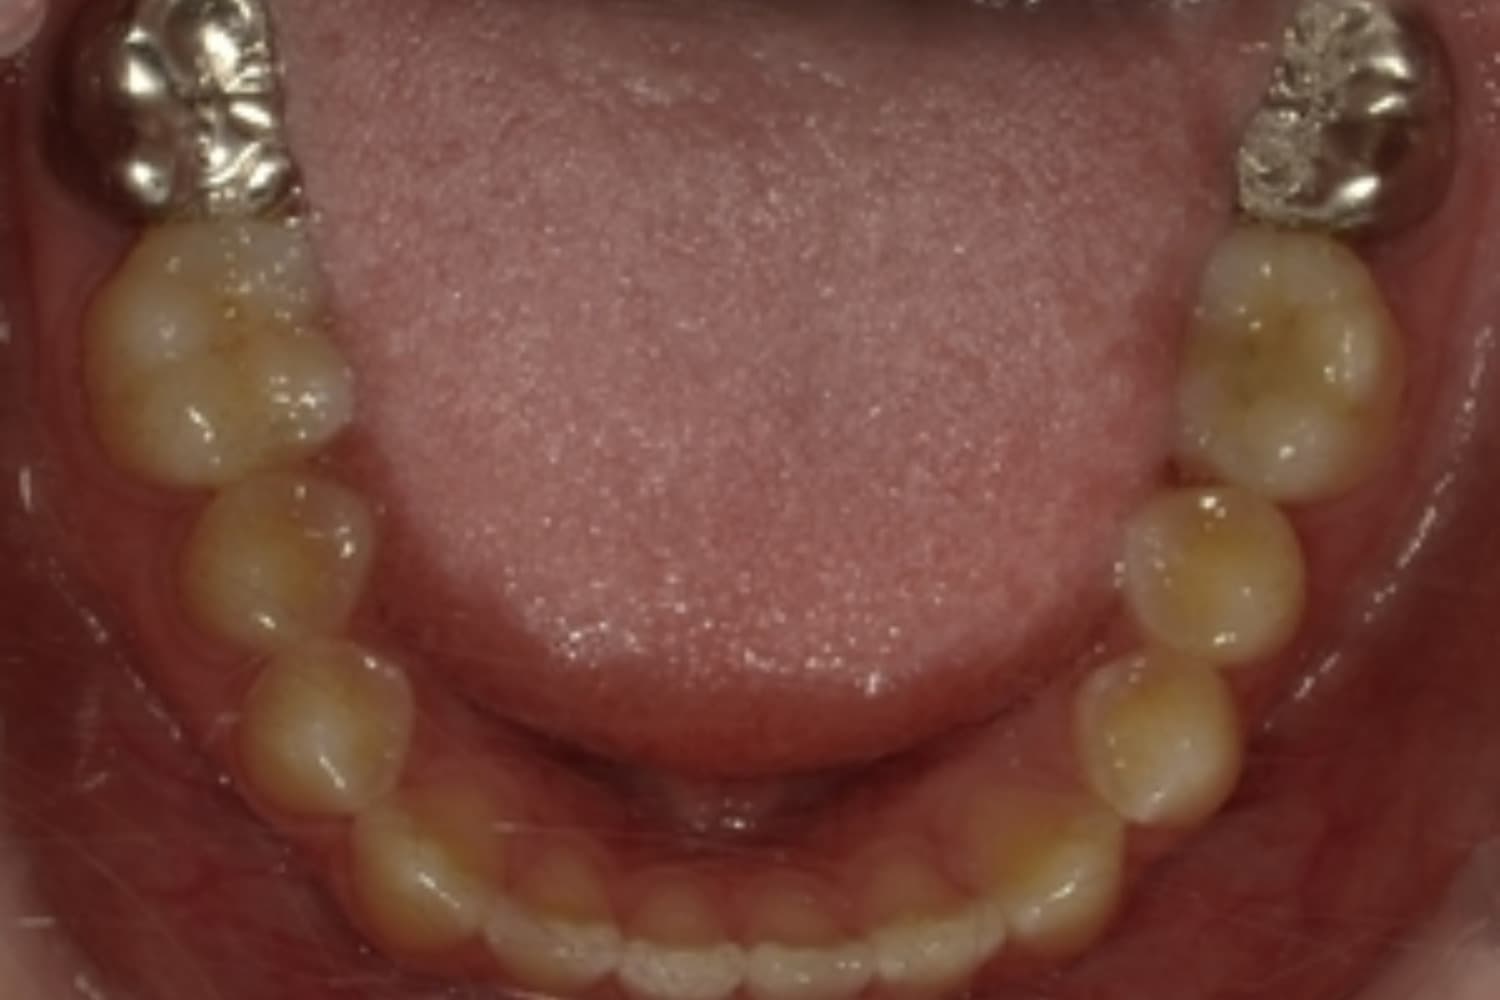

ガタガタとした歯並びや八重歯(1)

Before

After

ガタガタとした歯並びや八重歯をマウスピース矯正(インビザライン)にて治療

主訴

下の前歯のガタガタが気になる

治療期間

2年5カ月

費用

90万円

副作用・リスク

・矯正治療による歯の動きには個人差があり、想定より治療期間が延びることがあります。 ・矯正治療で歯を動かす際に痛みをともなうことがあります。 ・指示された通りに保定装置を装着しないと、歯並びや噛み合わせの後戻りを引き起こす可能性があります。